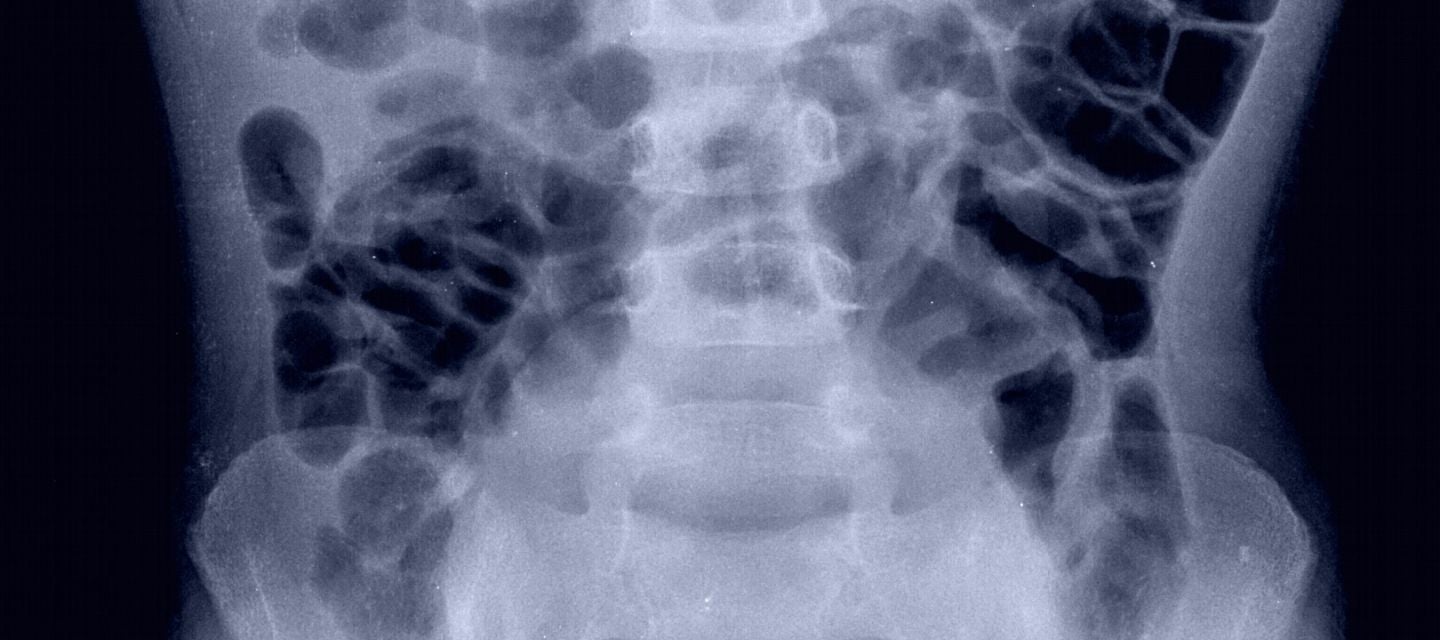

Colonic transit study x-ray

A colonic transit study uses x-rays to assess your bowel's motility rate. If constipated, it can help distinguish between slow colonic transit and a defecation disorder.

A colonic transit study is a special x-ray examination. It assesses the time it takes for food to travel through your digestive system.

It is most often used with patients who are suffering from chronic constipation.

When you schedule your appointment, you'll receive a capsule with 24 radiopaque polyvinyl chloride O-rings that show up on x-ray images.

On the a day of your choosing (day 0), swallow the capsule. The next day is day 1, and on day 5, attend our clinic for an abdominal x-ray.